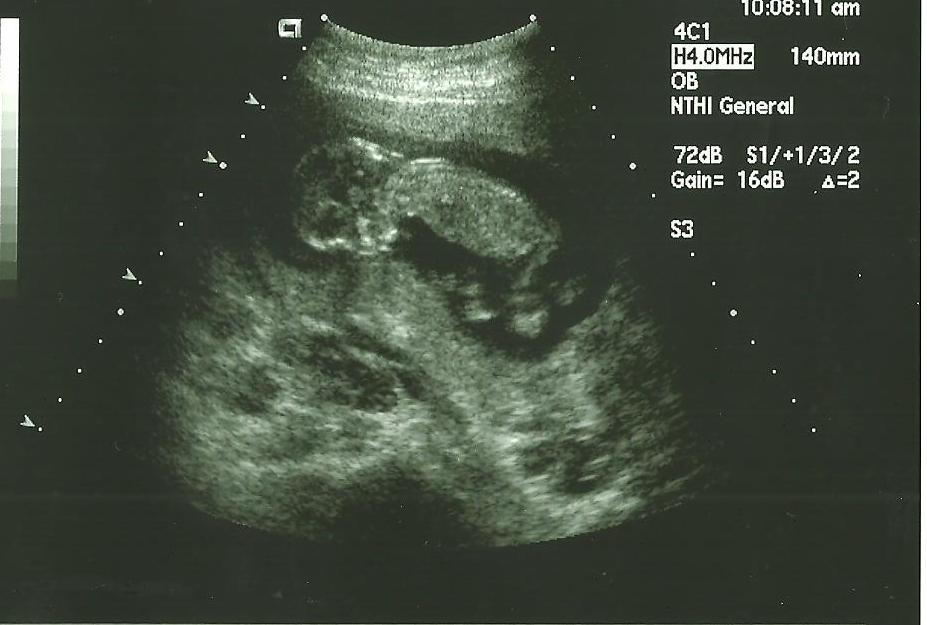

ultrasound pic at 14 weeks- what do you think?